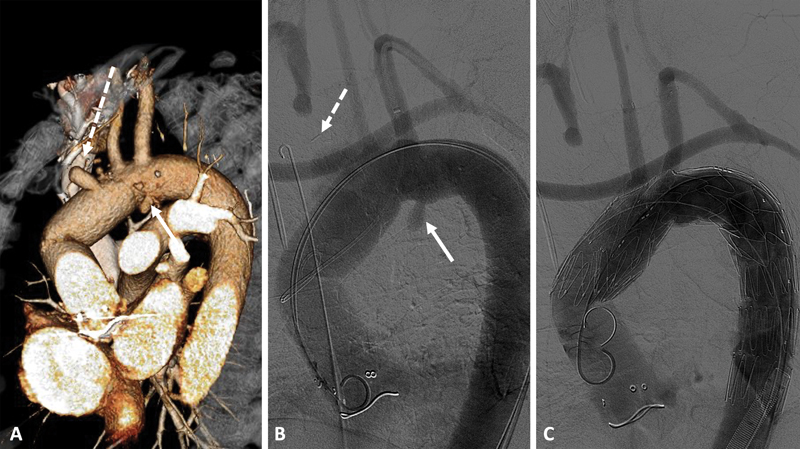

Abstract Image